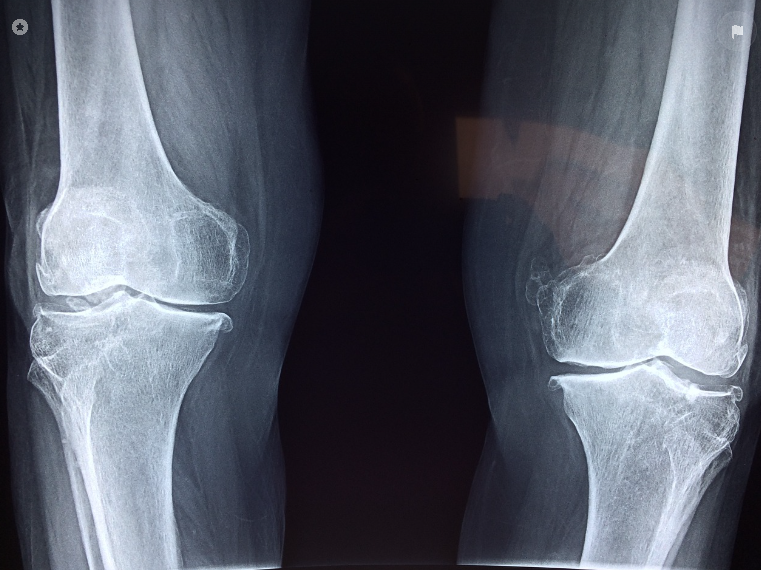

손가락, 무릎이 욱신욱신… 아침마다 뻣뻣한 느낌? 이거 뭔가 심상치 않다구요?!

- 관절이 점점 붓고 아프다 → 결국 변형됨 😭